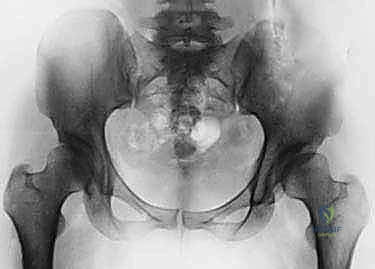

2. الأشعة السينية (X-rays): بأوضاع محددة لقياس زوايا التغطية (مثل زاوية CE وزاوية Tönnis) وتحديد درجة خلل التنسج.

4. الأشعة المقطعية ثلاثية الأبعاد (3D CT Scan): تُستخدم للتخطيط الجراحي الدقيق قبل العملية.

بعد تحرير التجويف، يقوم الدكتور هطيف بتدويره في ثلاثة أبعاد (3D) ليغطي رأس عظمة الفخذ بشكل مثالي. يتم التحقق من التغطية الجديدة باستخدام جهاز الأشعة السينية الفلوروسكوبي داخل غرفة العمليات لضمان الزوايا المثالية.

الخطوة الخامسة: التثبيت (Fixation)

بمجرد الوصول إلى الوضع المثالي، يتم تثبيت التجويف في مكانه الجديد باستخدام مسامير طبية (Screws) مصنوعة من التيتانيوم أو الفولاذ المقاوم للصدأ. هذه المسامير تمسك العظم بقوة حتى يلتئم العظم المقطوع بمرور الوقت (عادة خلال 6 إلى 8 أسابيع).